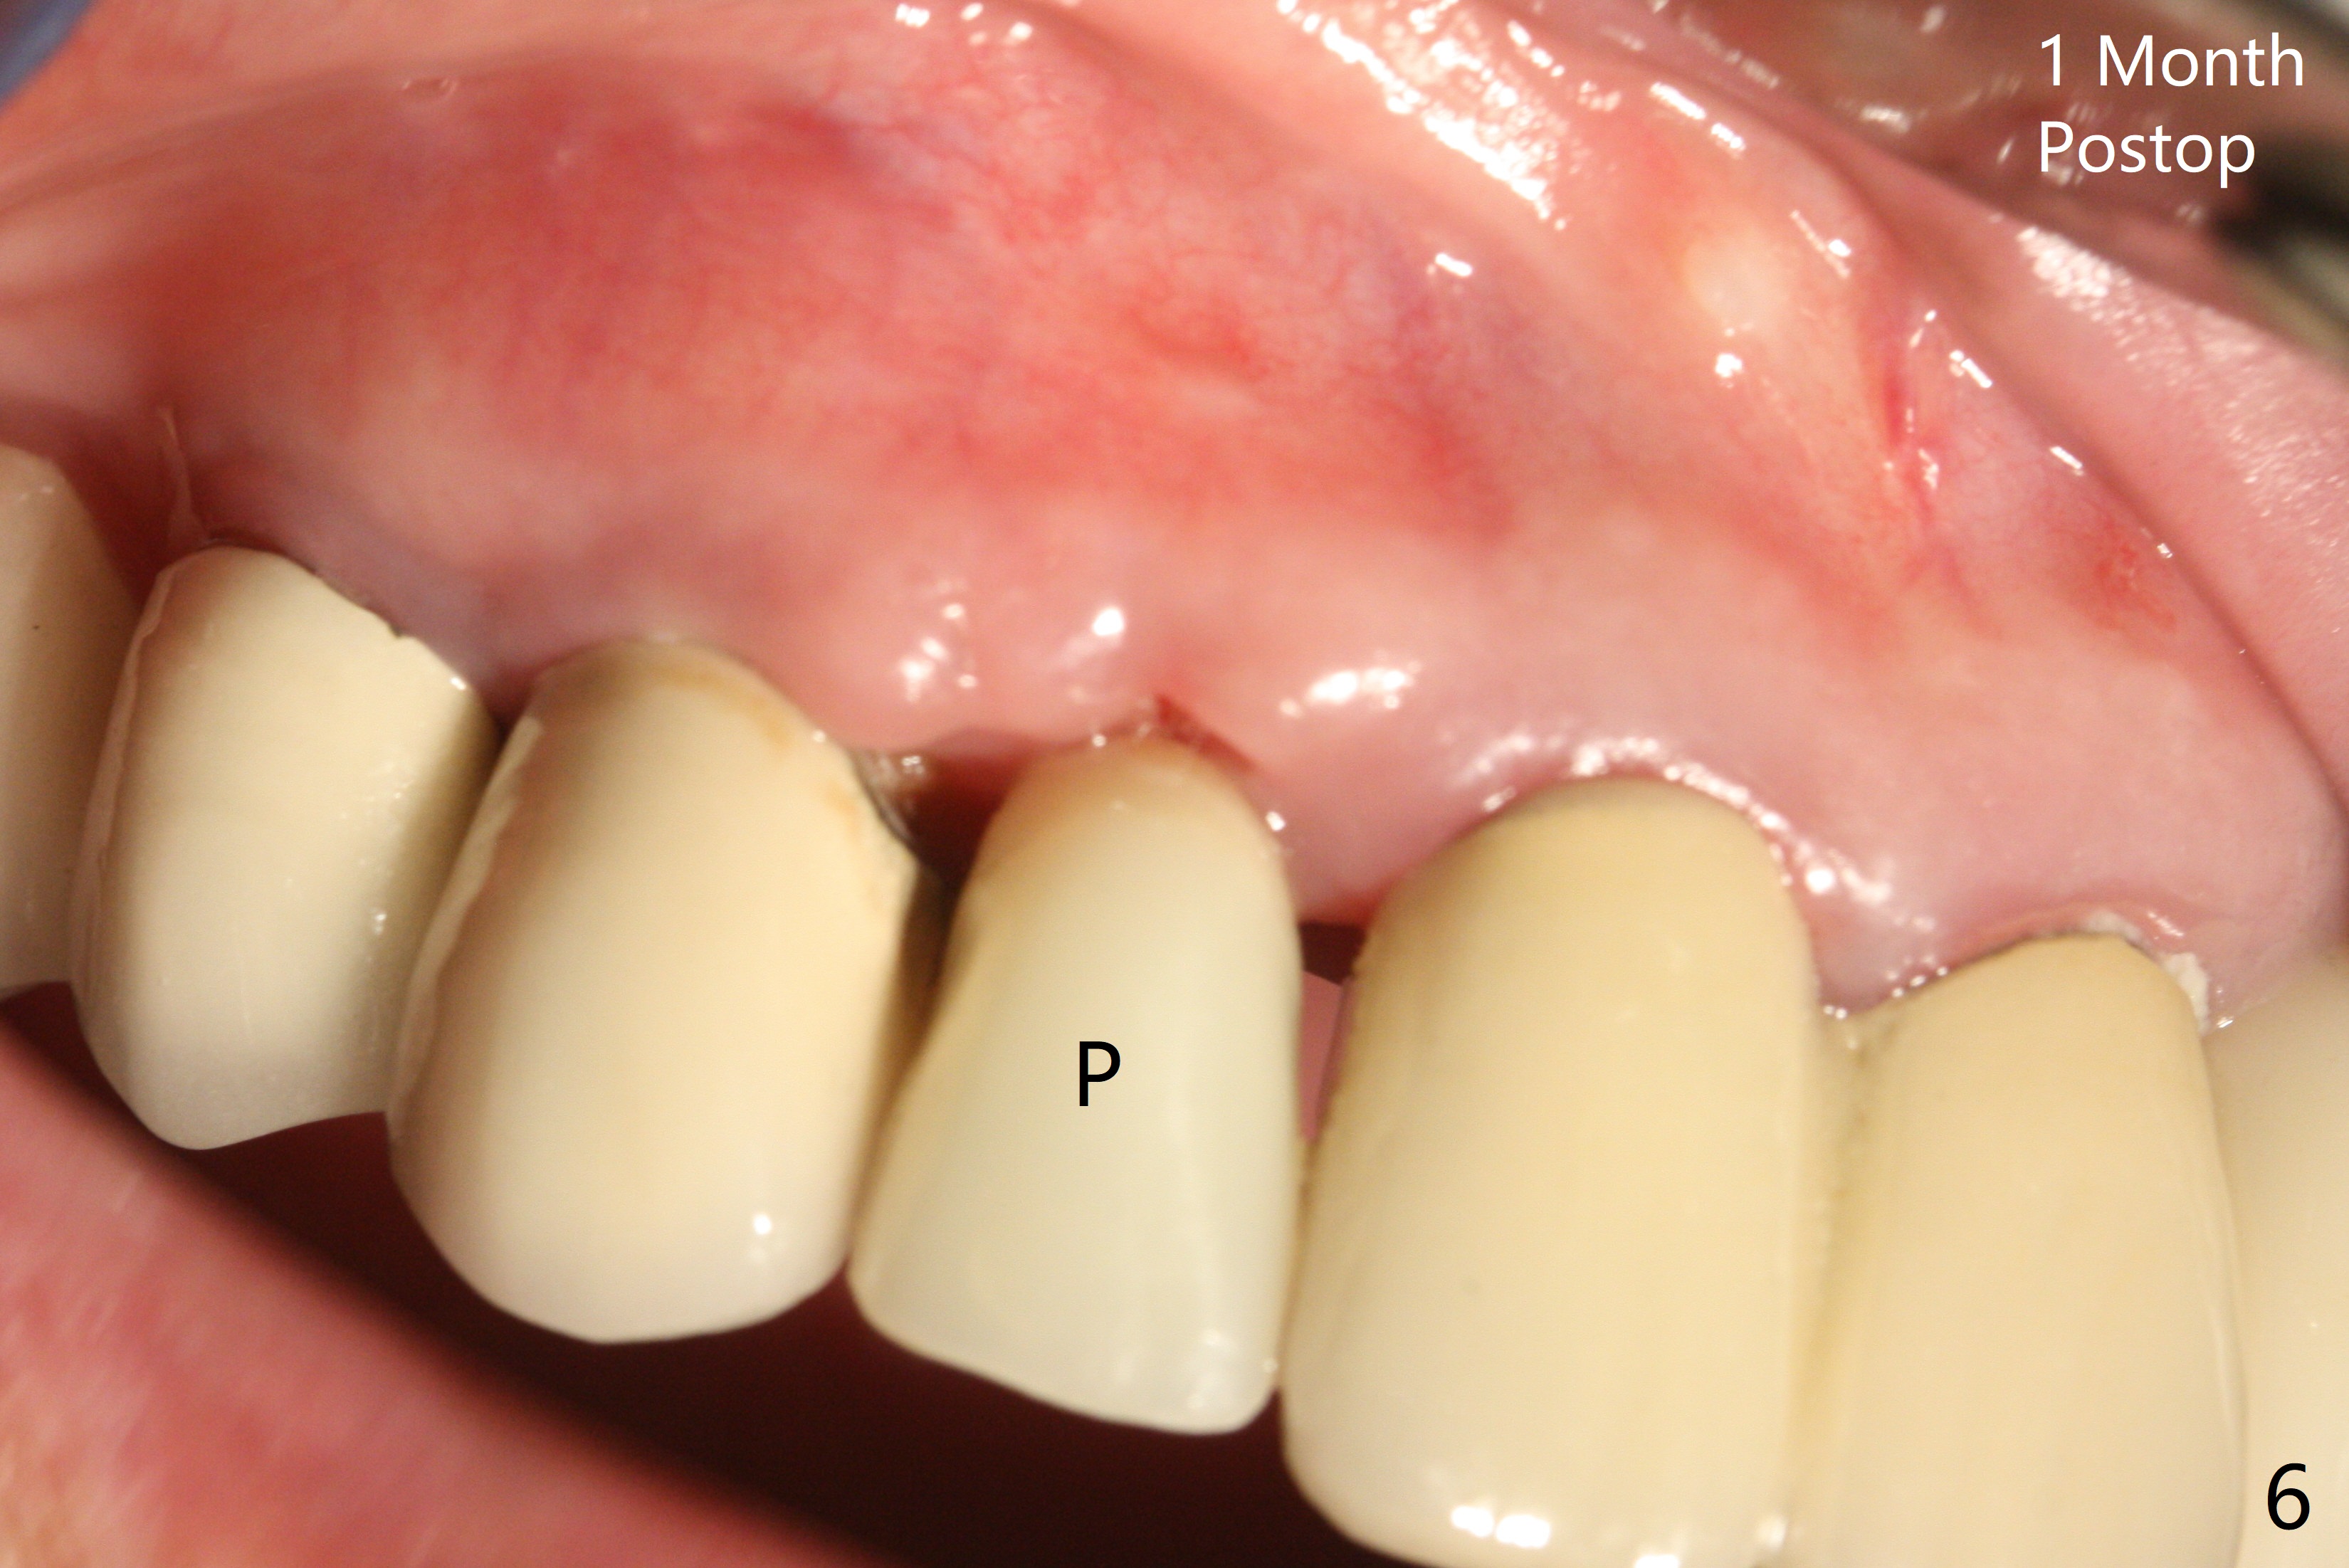

The edentulous area at #7 is narrow both buccopalatally and mesiodistally, whereas the crowns of the neighboring teeth are long (Fig.1,2). For the latter reason, it is difficult to remove the apical portion of the root, including gutta percha with surgical handpiece (Fig.3 *) for socket shield (Fig.2 *). To avoid the perspective implant touching socket shield, initial osteotomy is palatal. When a 2 mm drill is being used, the coronal end of the palatal plate starts to perforate. A 2.5x14 mm 1-piece implant is placed with 30 Ncm (Fig.4). The palatal plate is thin (Fig.5). Preop CT will help determine the position of initial osteotomy. The buccal gingiva seems to have been re-attached to the underlying alveolus and the provisional 1 month postop (Fig.6). The teeth #8 and 9 fracture (an implant is placed at #8 and bone graft at #9, while the implant at #7 is osteointegrating (Fig.7). In fact the shield is exposed without symptom. A year postop, another dental provider sends a photo of apparently hemorrhagic gingiva around #7 crown (Fig.8). A few days later with oral hygiene instruction, the gingiva around the exposed root piece is healthy (Fig.9). The root surface is reduced; with socket shield, there is no buccal plate collapse; in contrast the neighboring buccal plate (at #8 and 9) is concave (Fig.10). There is minimal exposure 11 days postop (Fig.11). The gingiva palatal to the shield is erythematous, a possible sign of periimplantitis. The socket shield at #7 appears to be fused with the buccal plate 11 months postop (Fig.12), as compared to the implant at #10 nearly 4 years postop (Fig.14). The buccopalatal widths at #7 and 10 are equivalent (Fig.13,15).